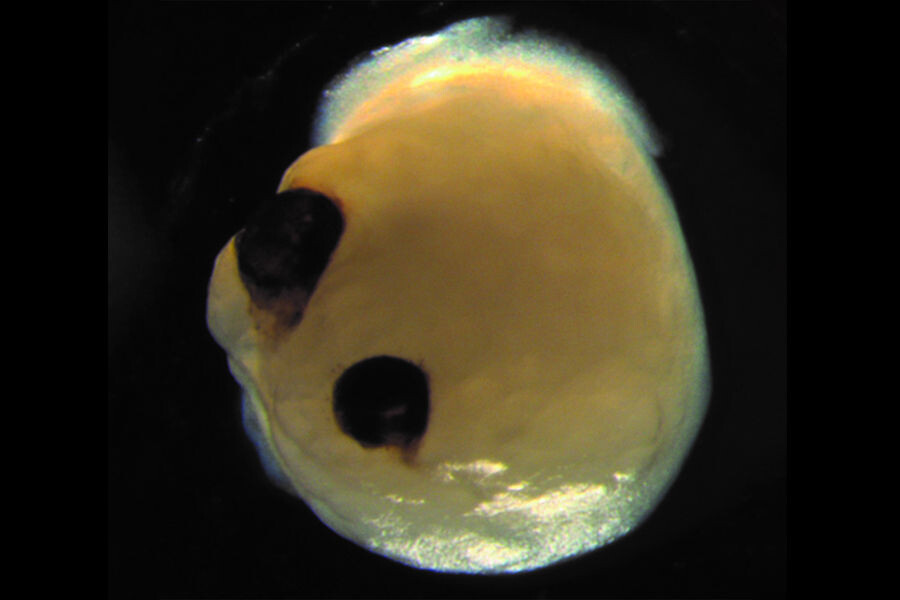

Представьте себе лабораторию, тишину ночи и ряды чашек Петри, в которых в питательной среде плавают крошечные белесые сферы. Это церебральные органоиды — выращенные из стволовых клеток мини-копии человеческого мозга. А теперь представьте шок исследователей, когда эти «сгустки мыслей» вдруг начали... отращивать глаза. Это не сюжет для нового хоррора от Netflix, а реальный прорыв в нейробиологии. Команда ученых из Университетской клиники Дюссельдорфа под руководством Джея Гопалакришнана совершила нечто невероятное: они заставили мини-мозги не просто развиваться, но и самостоятельно формировать оптические чаши. Анатомия чуда: Когда биология берет инициативу. Самое поразительное в этом эксперименте — это спонтанность. Ученые не «пришивали» глаза к органоидам. Они создали правильные условия, и стволовые клетки сами запустили древнюю генетическую программу. Примерно на 30-й день развития у мини-мозгов начали появляться симметричные выросты, а к 60-му дню они превратились в полноценные оптиче

Примерно на 30-й день развития у мини-мозгов начали появляться симметричные выросты, а к 60-му дню они превратились в полноценные оптические чаши. Эти структуры не были просто декоративными пятнами. Исследование показало, что они содержали: